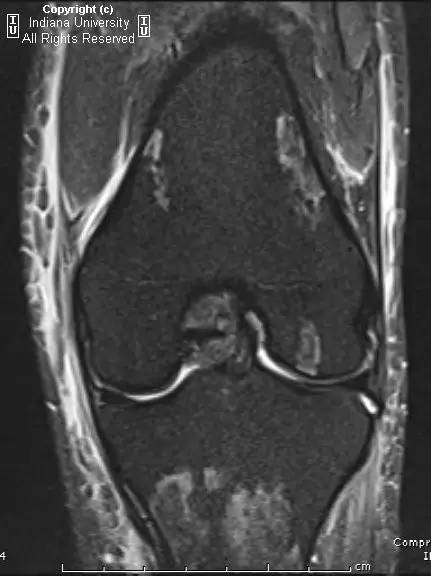

- 膝关节MRI:双侧膝关节股骨干骺端、股骨髁、胫骨干骺端、髌骨T1信号减低、T2信号增高,股骨髁关节面也有类似的信号异常。软组织弥漫性水肿。同时存在关节积液。

- AVN表现为软骨下局部缺血并骨髓水肿。骨梗死表现为松质骨内匐行性的边界或轮廓病变。

- MR骨梗死示不规则或匐行性T1低信号、T2高信号,周围骨髓水肿。AVN表现为软骨下T1信号减低、T2信号增高,伴水肿和关节面塌陷。